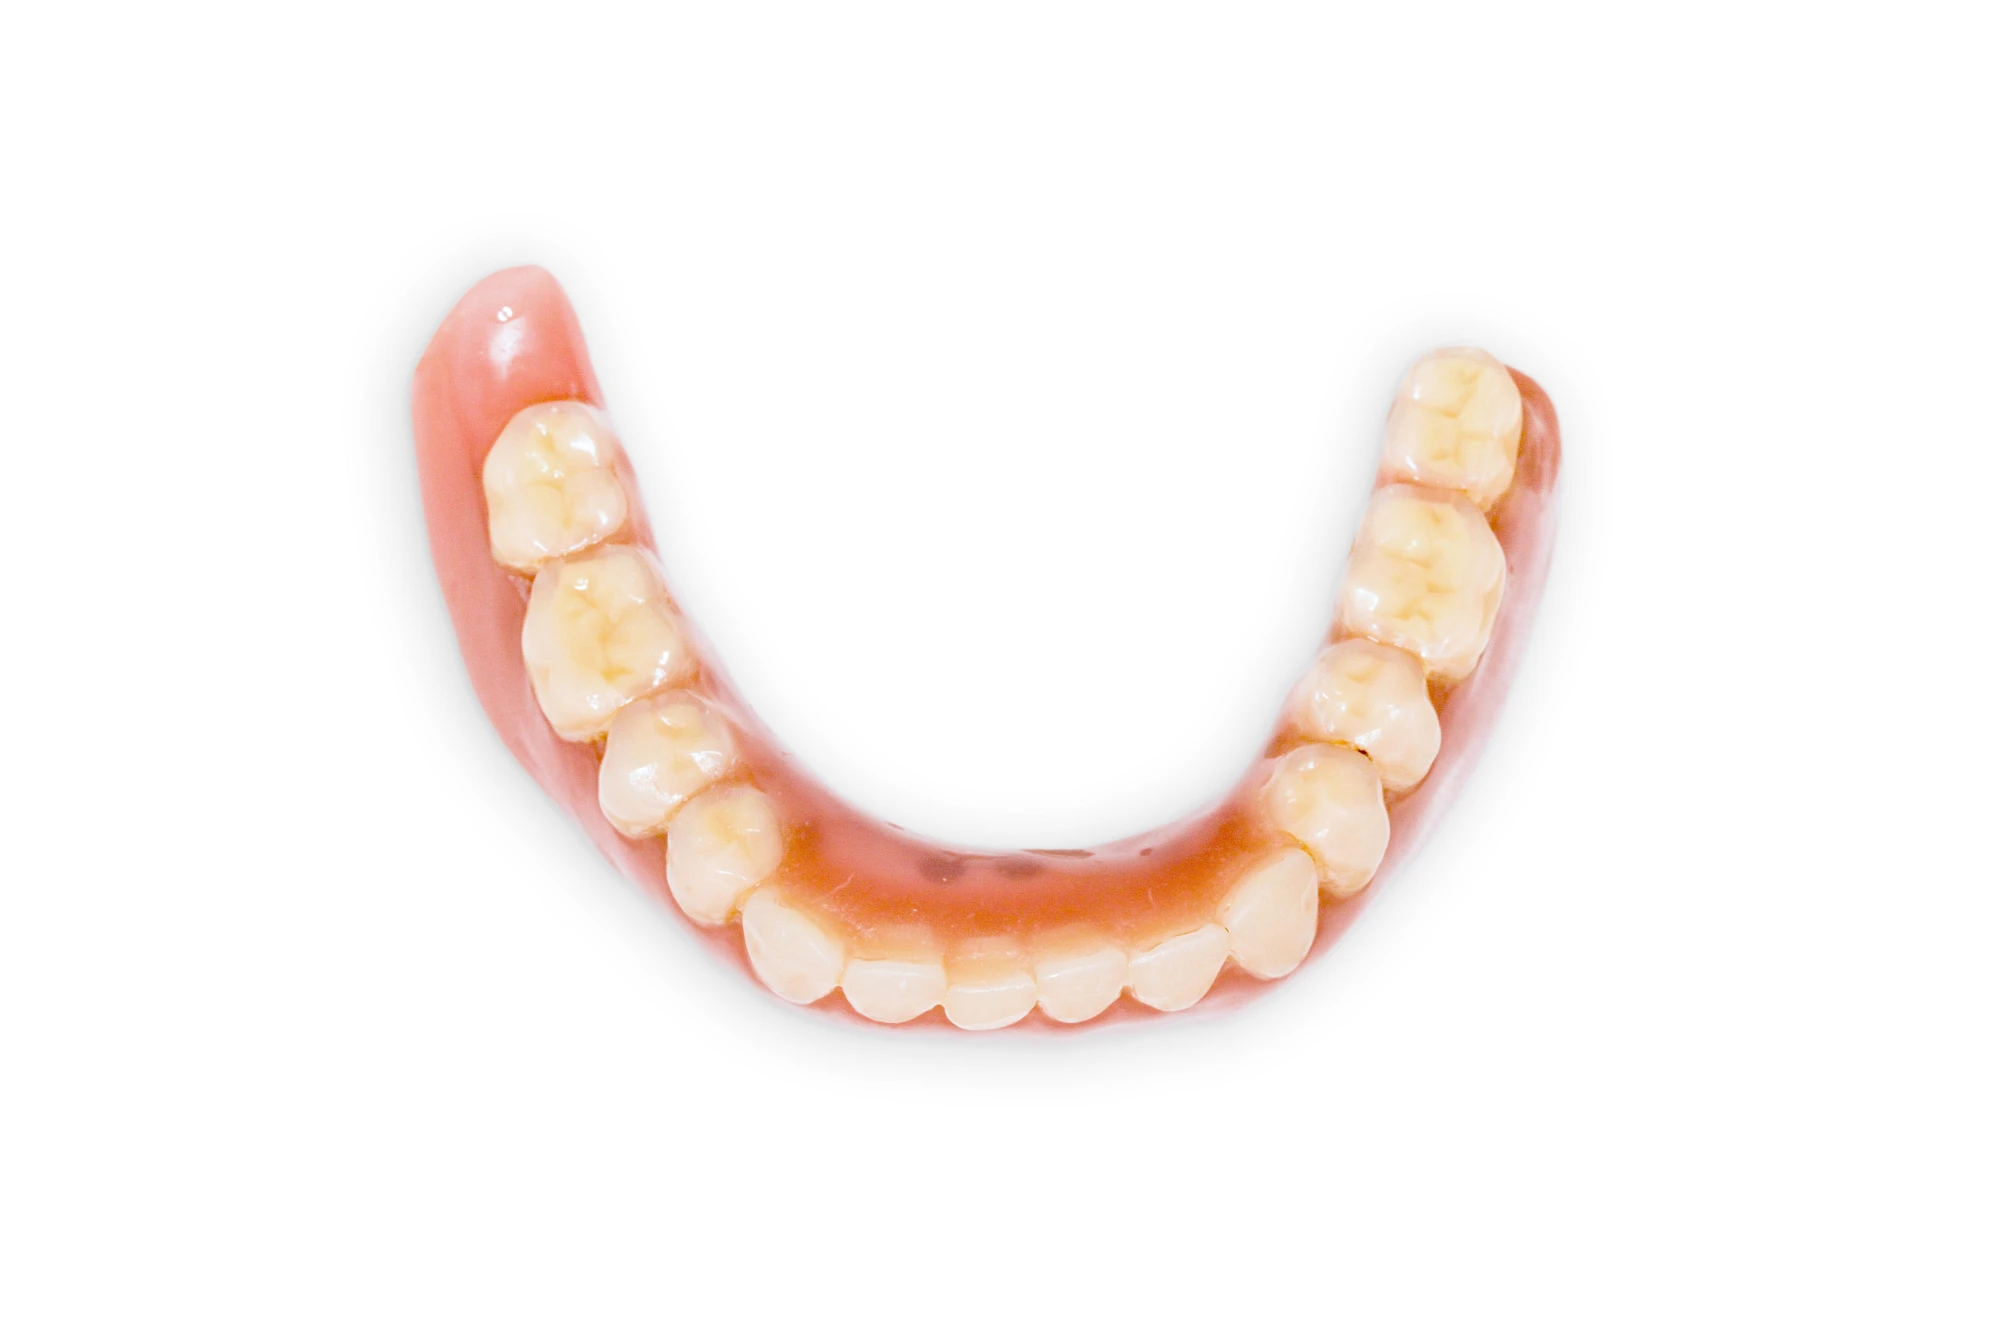

Implantate: Prothesen

Bei herausnehmbaren Prothesen werden Implantate eingesetzt, um den Halt und den Tragekomfort der Prothesen zu verbessern. Dazu kommen verschiedene Verbindungselemente zum Einsatz:

- Teleskope

- Kugelköpfe

- Tellerförmige Lokatoren

- Stege

- Magnete (selten)

Neben rein implantat-getragenen zahnärztlichen Versorgungen werden bei herausnehmbaren Prothesen Implantate auch in Sinne einer "strategischen Pfeilervermehrung" ergänzend zu eigenen Zähnen zur Verankerung eines Zahnersatzes genutzt.

Varianten zur Verankerung von abnehmbarem Zahnersatz auf Implantaten